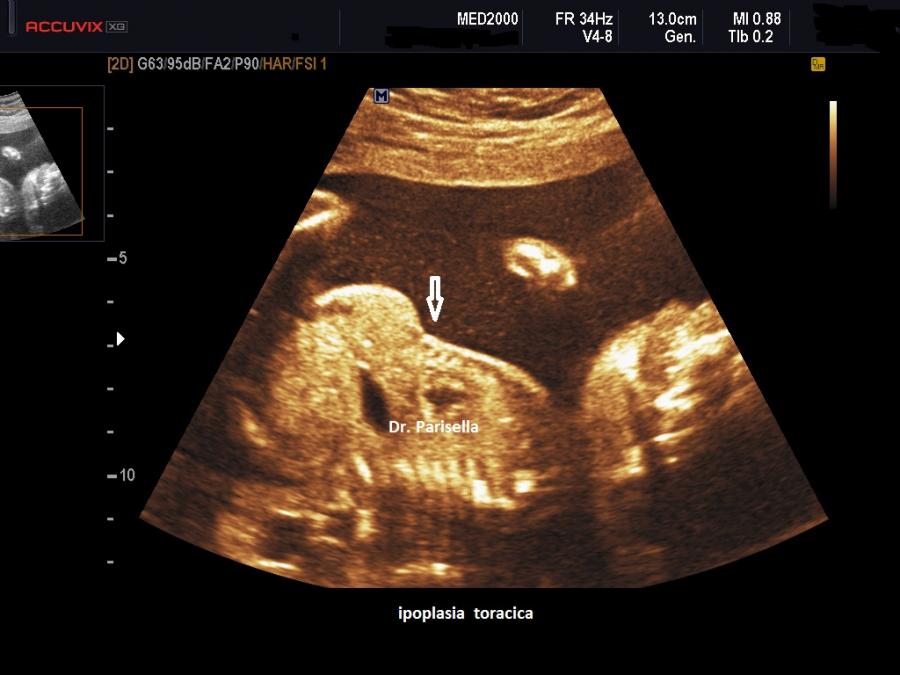

La Displasia Tanatofora tipo 1 è trasmessa con modalità autosomica dominante ed è caratterizzata principalmente da RIZOMELIA SEVERA, FEMORI CORTI (A CORNETTA DI TELEFONO), IPOPLASIA TORACICA SEVERA.

Dal punto di vista ecografico il tratto rizomelico è estremamente ipoplasico, ricurvo e con le metafisi slargate (Femore a Cornetta di Telefono) -  (il riconoscimento del Femore a Cornetta di Telefono rappresenta un segno importantissimo e sufficiente per porre con certezza la diagnosi di Displasia Tanatofora tipo I); vi sono coste corte con ipoplasia toracica e si osserva il classico gradino al passaggio tra torace ipoplasico e addome apparentemente prevalente; vi è in genere macrocrania con bozze frontali prominenti (frontal bossing) e naso a sella. Si associa polidramnios severo.